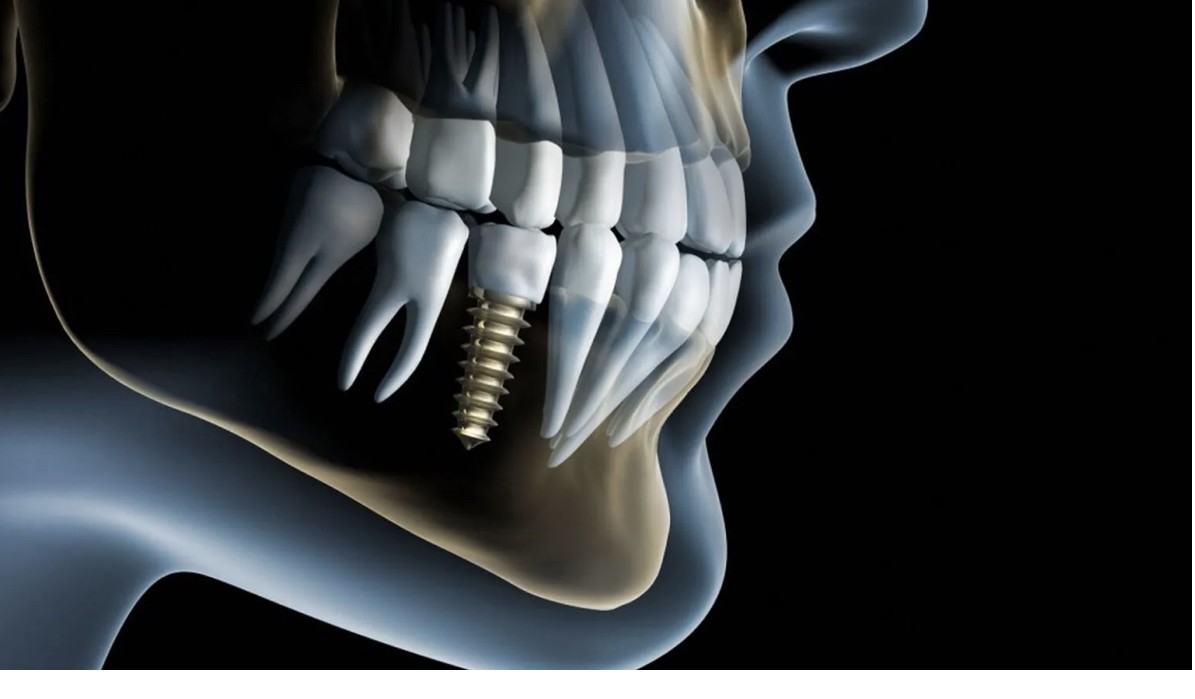

Clinica noastră stomatologică de familie oferă îngrijire completă și personalizată pentru toate vârstele, într-un mediu prietenos și relaxant. Punem accent pe prevenție, educație și tratamente moderne, folosind tehnologii de ultimă generație pentru a asigura confortul și siguranța fiecărui pacient. Echipa noastră de medici dedicați are o abordare empatică, bazată pe încredere și comunicare deschisă. Fie că este vorba de un control de rutină, tratamente estetice sau intervenții complexe, scopul nostru este să redăm zâmbetul sănătos și încrederea fiecărui membru al familiei.